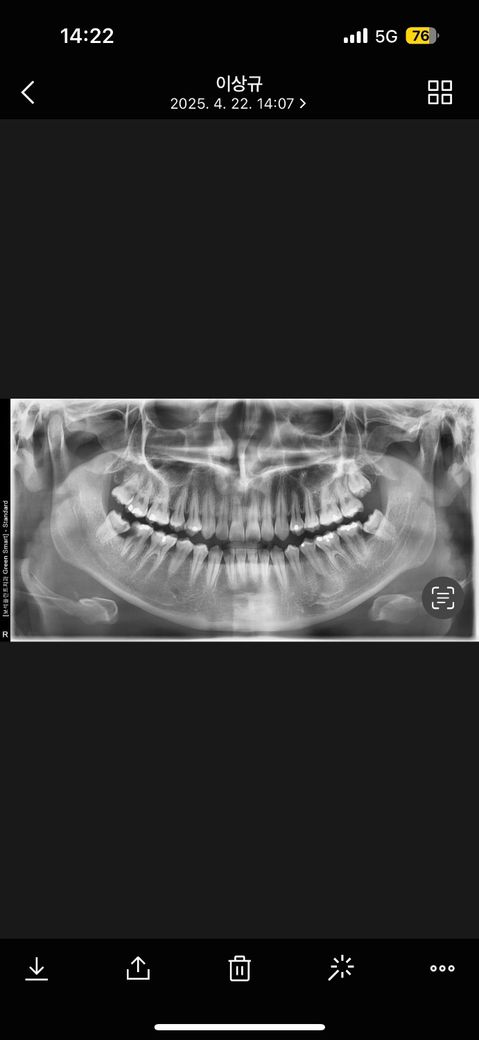

사랑니 통증 때문에 발치를 하기 위해 방문한 치과에서 우측 아래 사랑니 옆 어금니도 함께 발치를 하고 임플란트를 해야한다고 권하셔서 다른 전문가분들의 소견은 어떨까싶어 질문 남깁니다 물론 약간의 치아 파절과 경미한 흔들거림은 있습니다만 x-ray상으로 봤을때도 발치 후 임플란트가 최선일까요?!?

양쪽 아래 어금니가 사랑니로 인해서 충치가 생겨있습니다. 사랑니로 인한 충치이기 때문에 사랑니를 발치하는 것이 좋으며 발치를 한뒤에 충치를 치료하는것이 좋습니다.

사랑니로 인해 앞의 어금니도 손상이 있어 보이며, 이 경우에는 앞의 어금니도 발치를 하고 임플란트가 필요로 될수 있습니다. 하지만 흔들림이 경미하고, 치주상태가 양호한 경우 크라운이 가능하기도 하기에 보다 정확한 상태 확인을 위해 치과 진료를 직접 다른 곳에서도 받아보길 권합니다.

사랑니는 빼면 되고요. 문제는 그 앞 어금니네요.

사랑니와의 단차로 인해 음식물이 많이 꼈을 것이고 그래서 깊은 충치가 생겼는데요.

해당 치아를 살리고자 한다면 신경치료하고 크라운을 씌워야 할 가능성이 높고 그 과정에서 크라운 높이 확보를 위해 잇몸이나 뼈를 일부 갈아내야 할 수도 있습니다.